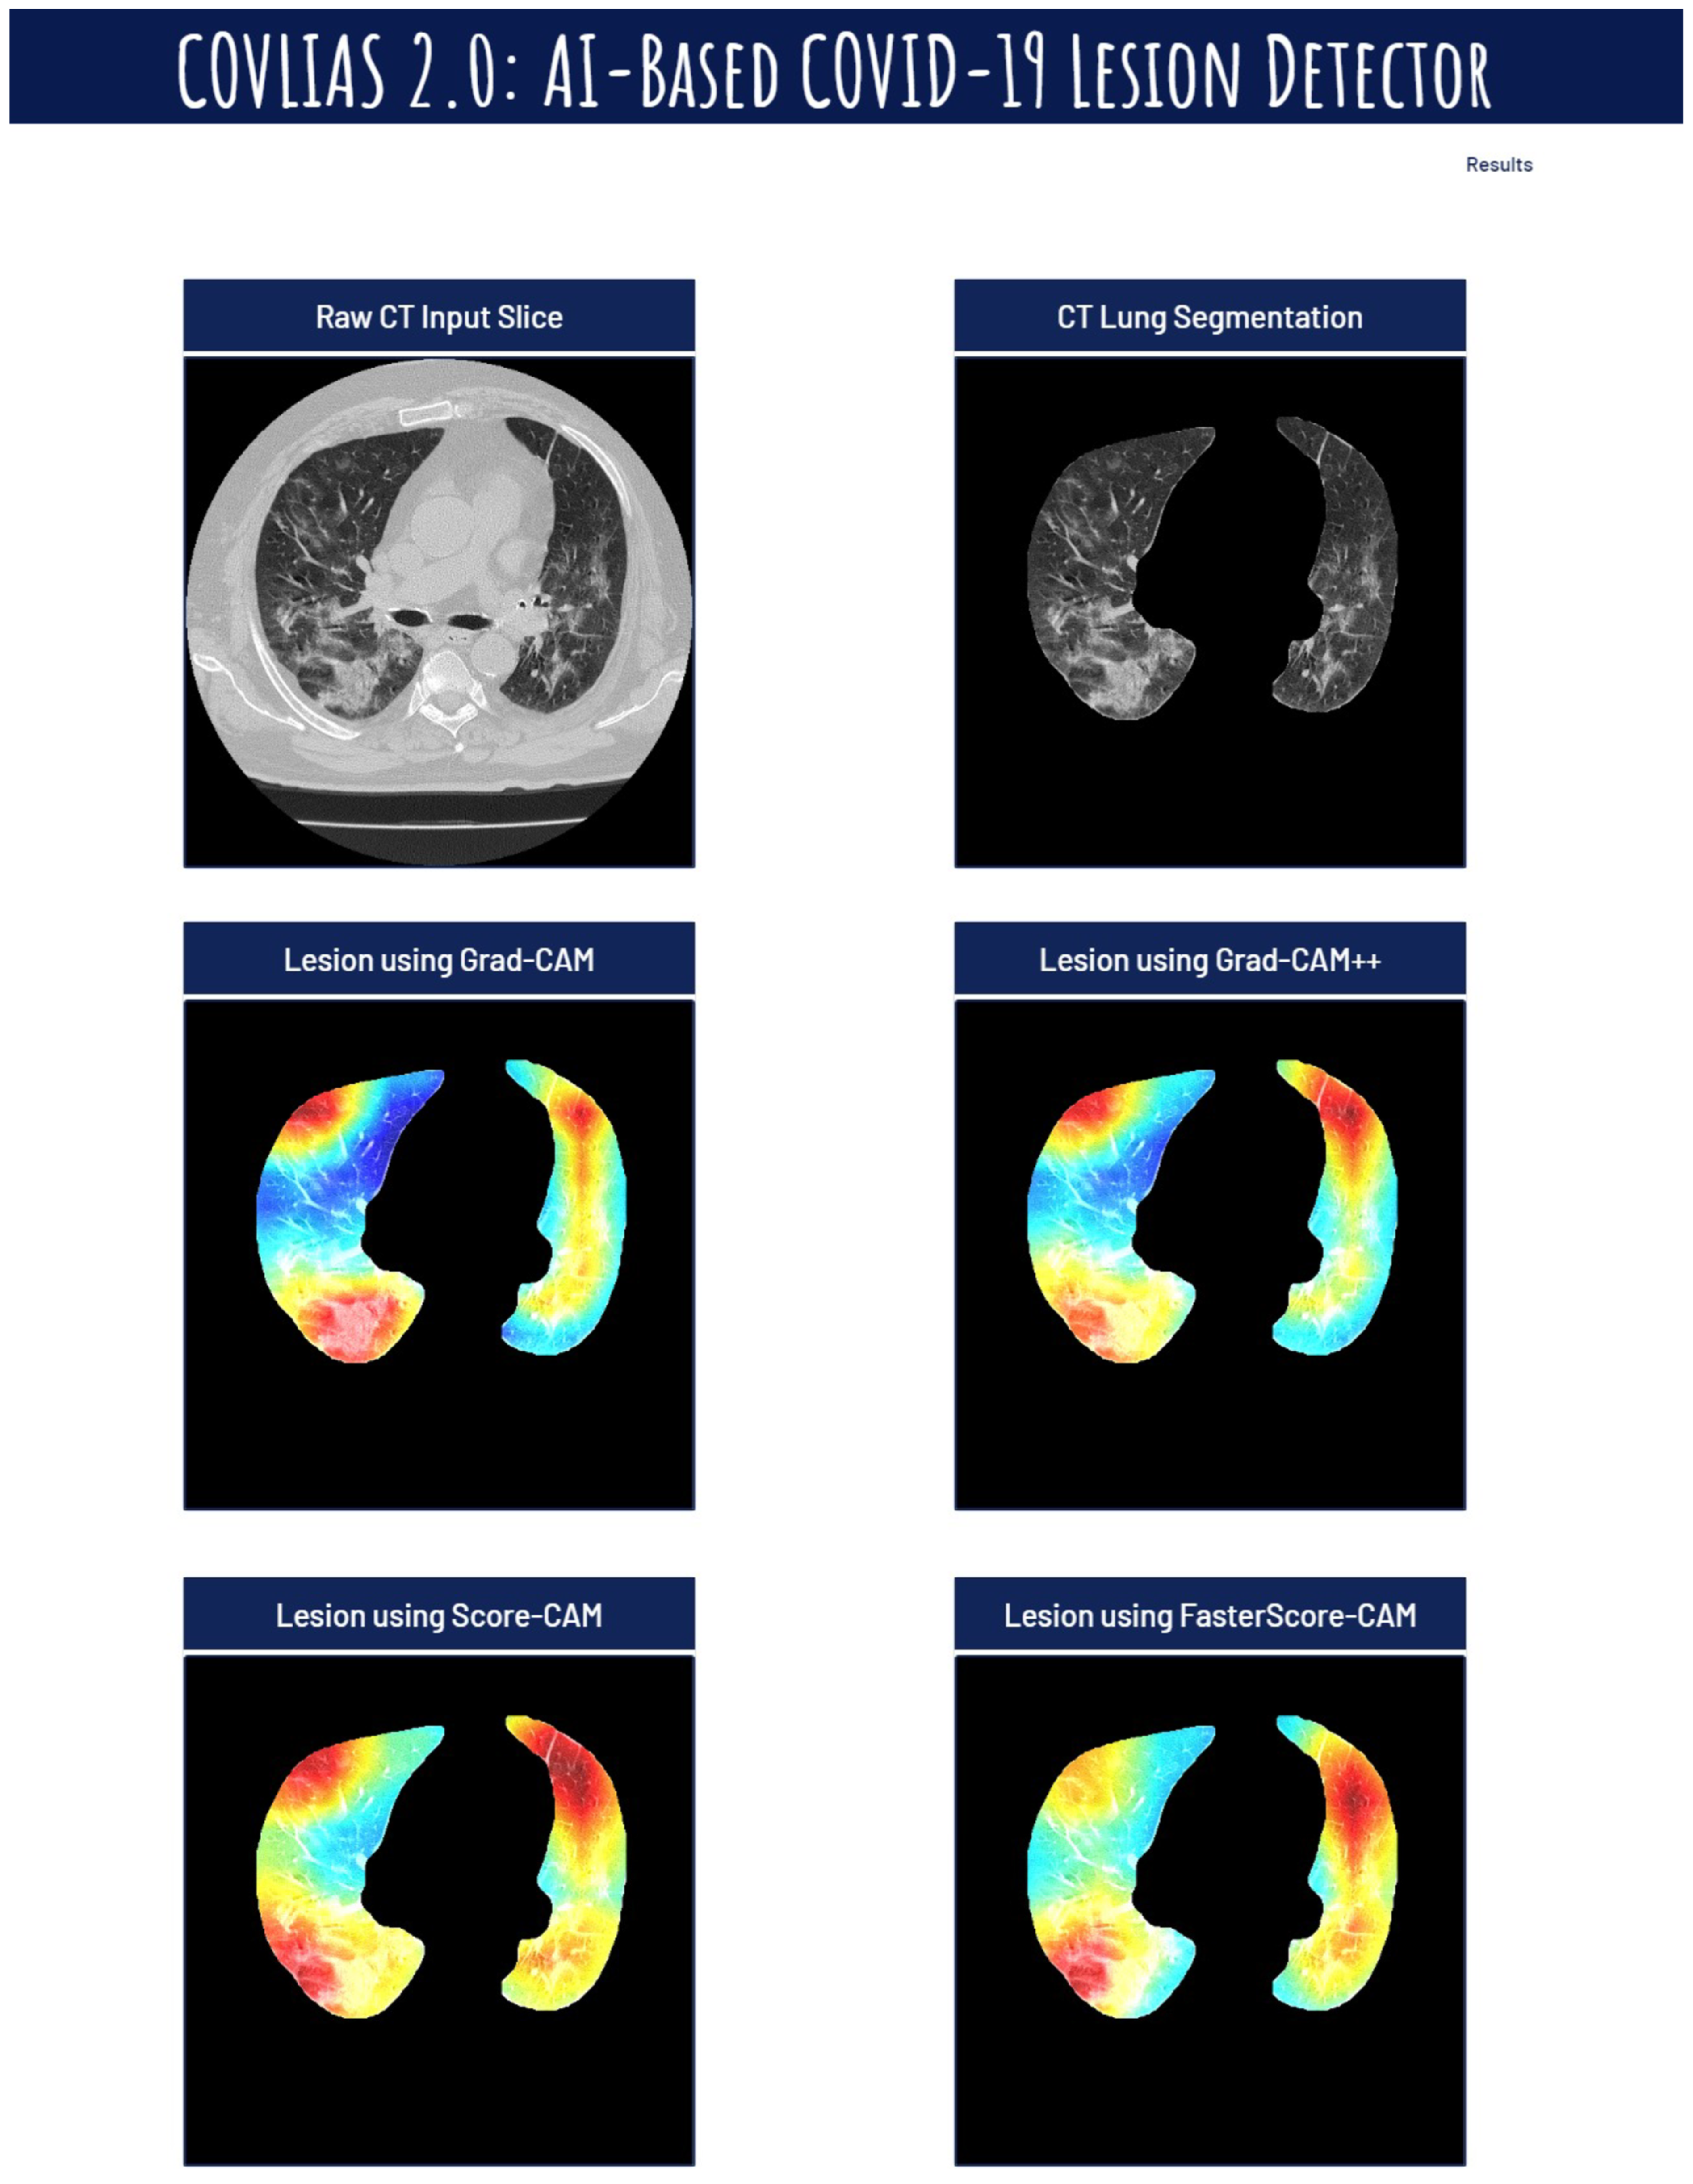

Visual Results Representing Lesion Using the Four CAM Techniques